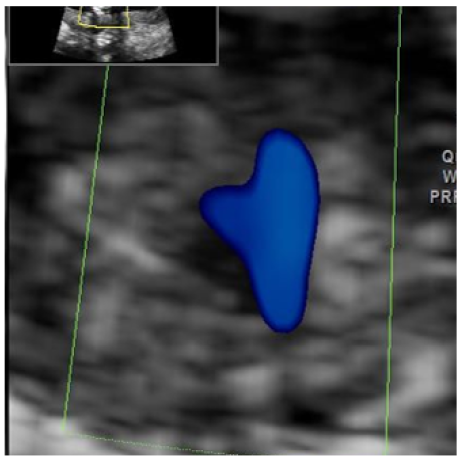

Visual Biofeedback for Pelvic Floor Training

Luana Malagutti Machado and Samantha Condé Rocha Rangel. 12(4): 04.